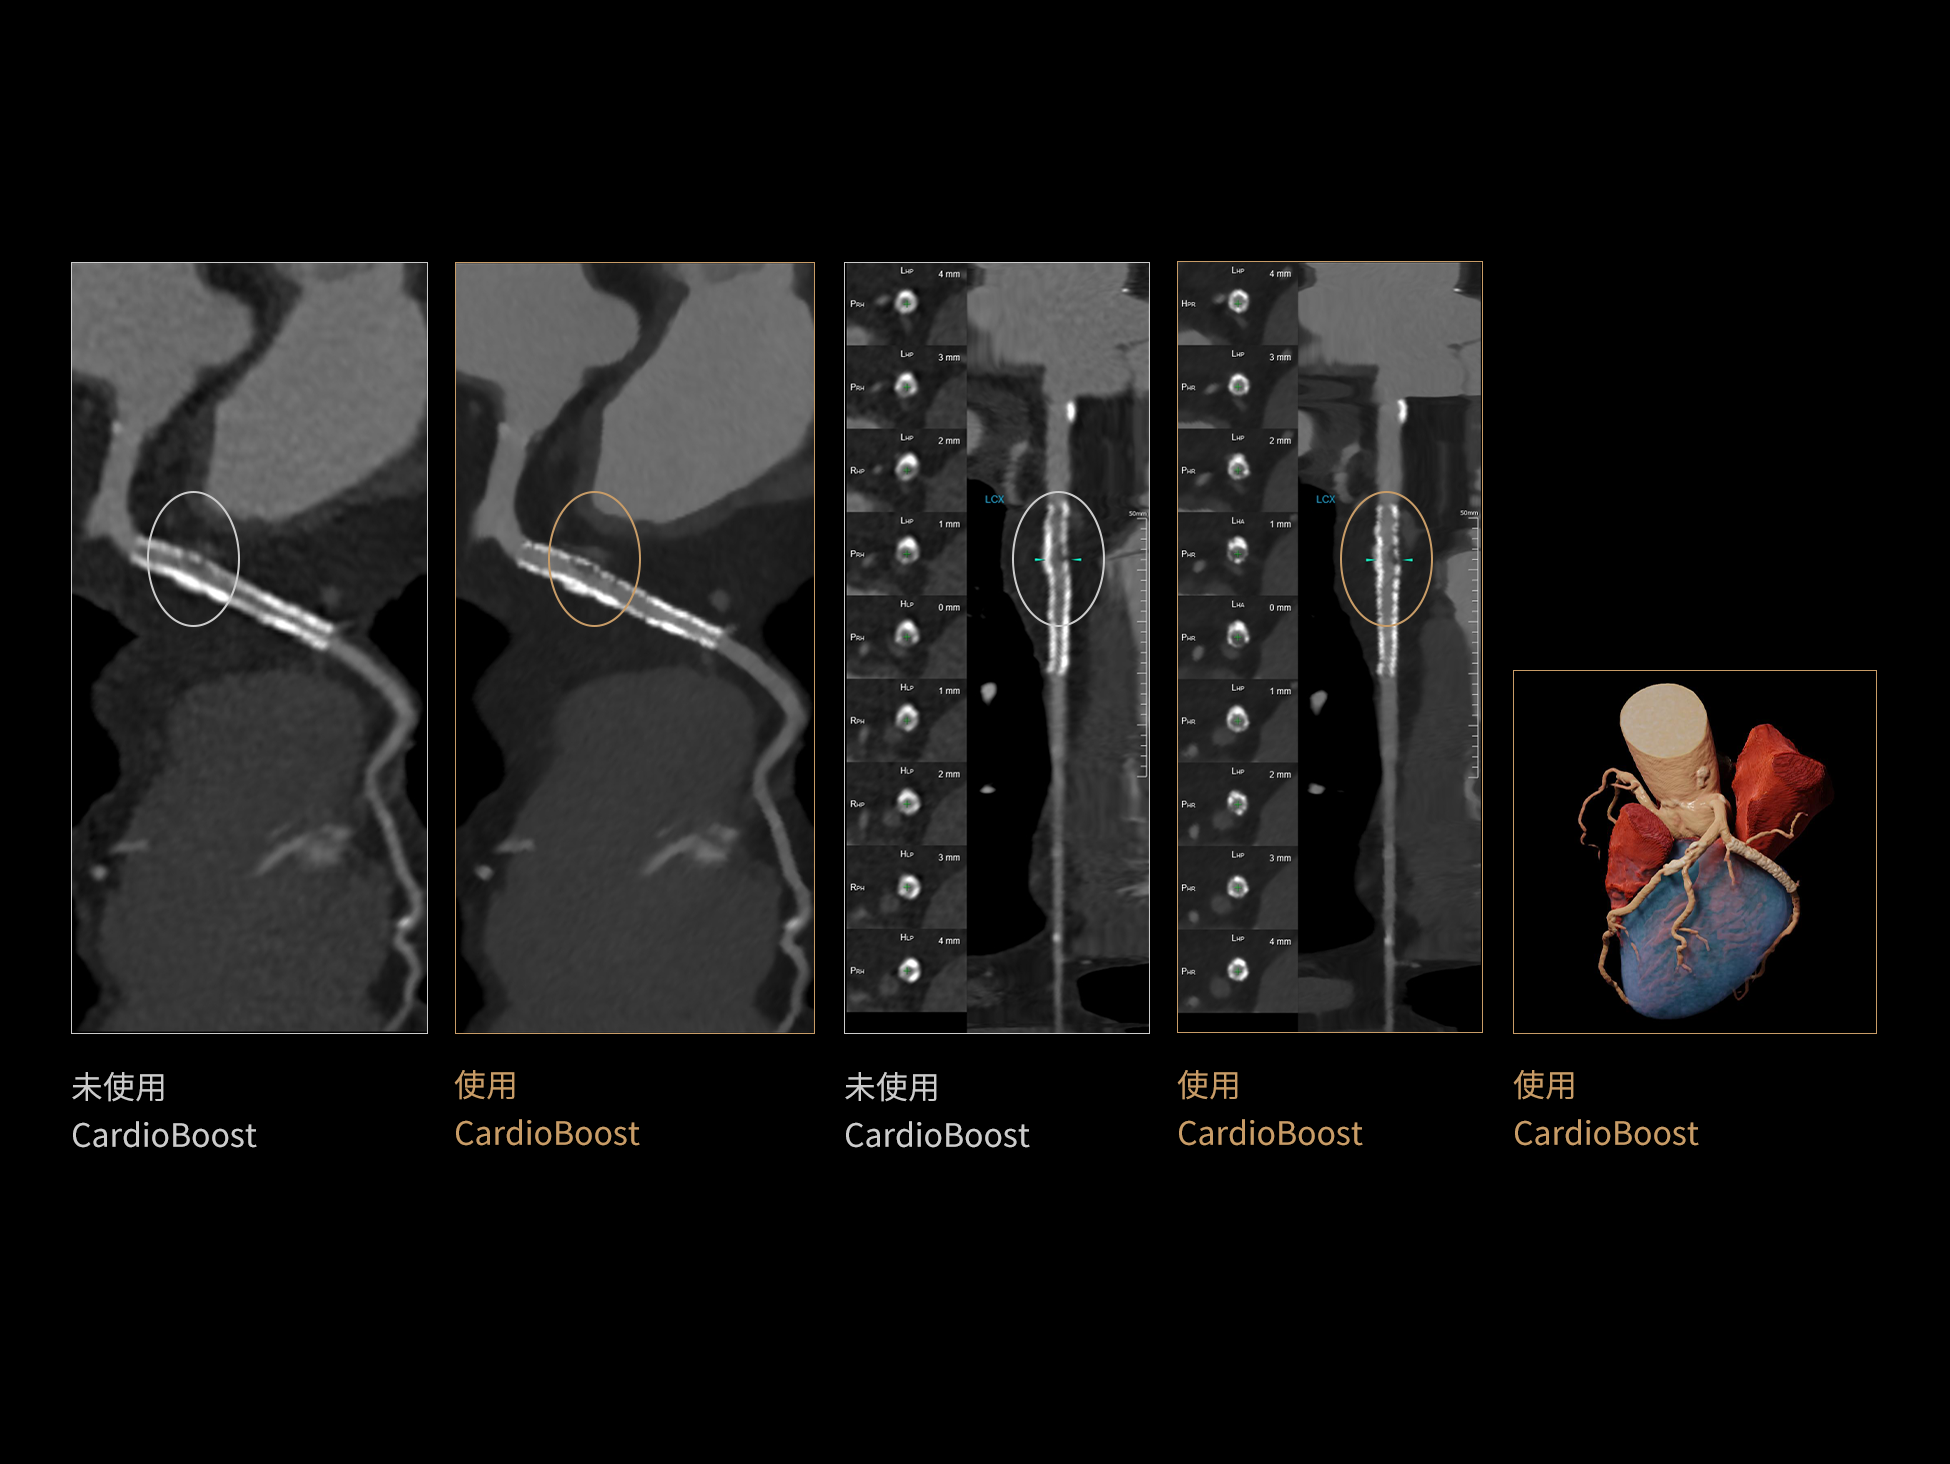

CardioBoost:专属网络设计,重塑心脏影像表现

目前心脏的 CT 检查还存在辐射剂量偏高、空间分辨率不足、 致密钙化伪影影响冠脉狭窄程度评估等方面的限 制[1][2]。CardioBoost 技术专为心脏 CT 高清成像而开发,通过 3D 神经网络的深度学习技术,利用先进的注意力机制在识别关键成像特征方面的出色表现,能够精确地聚焦于斑块、支架以及微小血管等关键细节,清晰展示这些结构与冠脉血管的边界,从而显著提高诊断的准确性,并提升医生的诊断信心。创新的 CardioBoost 心脏图像重建算法,不仅实现了图像清晰度的提升和伪影的去除,更能在减少辐射剂量的同时,保证心脏图像的高质量和图像纹理的自然。

CardioBoost核心创新

采用 3D 神经网络的空间结构优势与精细的组织分类能力,CardioBoost 技术优化了组织对比,高清展示血管斑块,使斑块与血管边缘的轮廓清晰可辨,提升斑块诊断与评估的精确性。

借助 3D 神经网络设计、空间注意力机制聚焦与特征强化作用,CardioBoost技术提升图像的空间分辨率,实现冠脉支架的高清成像,对支架形态与管腔通畅度的评估更精准。

CardioBoost 整合先进的 3D 神经网络和空间注意力机制,大幅增强数据处理的速度与精确度。该技术能有效抑制由致密钙化引起的晕状伪影,清晰展现钙化斑块的原始结构和大小,对冠脉狭窄的评估更加精确可靠。

对比度强化模块

分辨率强化模块

伪影抑制模块